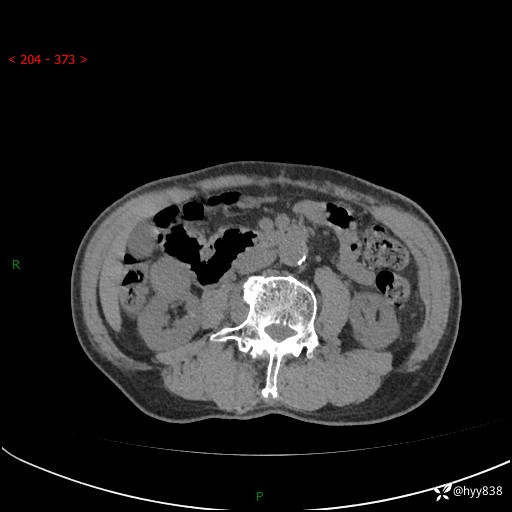

辅助检查:CT

临床诊断:肾肿物

肾脏CT平扫

增强(皮质期+髓质期+排泄期)

三期CT值:132hu 107hu 81hu